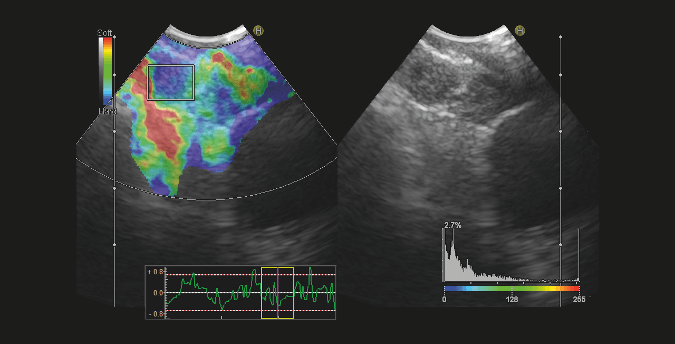

Ecobroncoscopia

Posibilita la toma de muestras de lesiones fuera de la via aérea gracias a la ayuda del ecógrafo asociado al sistema de broncoscopia.